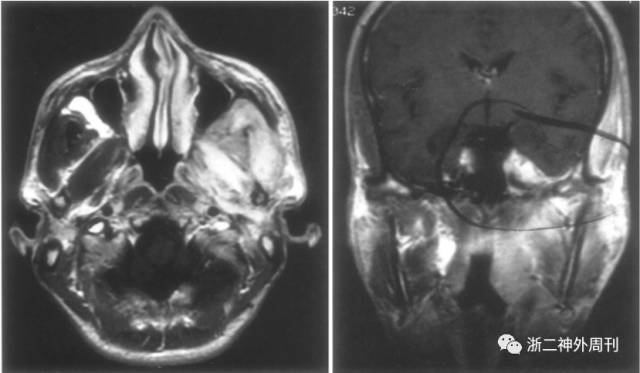

患者,女,11岁,因“头痛3月余,面部浮肿10天”入院。患者3月余前无明显诱因下出现头痛,无恶心呕吐,无畏寒发热,无四肢抽搐等。遂至我院儿科就诊,查CT及MRI示:右眶尖-海绵窦-颞下窝病变,考虑炎症性病变可能,肿瘤不能除外(图1)。今为求进一步诊治,拟以“海绵窦肿瘤”收住入院。

图1. 术前MRI检查:A)T1加权轴位;B)T2加权轴位;C)增强像轴位;D-E)增强后冠状位和F)矢状位示右眶尖-海绵窦-颞下窝病变,呈等T1、略长T2信号,增强后明显强化,邻近脑膜增厚伴强化。

发生于颅内的IMT较为罕见,颅内IMT多见于眶内和颅底[1,2]。Desai SV等[3]总结了33篇文献共计87例发生于鼻窦和颅底腹侧面的IMT,得出IMT在颅底的分布热图(图4)。

多数颅内IMT在CT上呈高密度病变,约有超过4/5伴有骨质破坏。MRI显示颅内IMT在T1像上呈等信号,T2像呈低信号,增强像上伴有强化,尤其当IMT位于海绵窦内时强化更为明显(图5)。

图5. 典型海绵窦IMT的影像学表现(箭头所指为IMT病变)